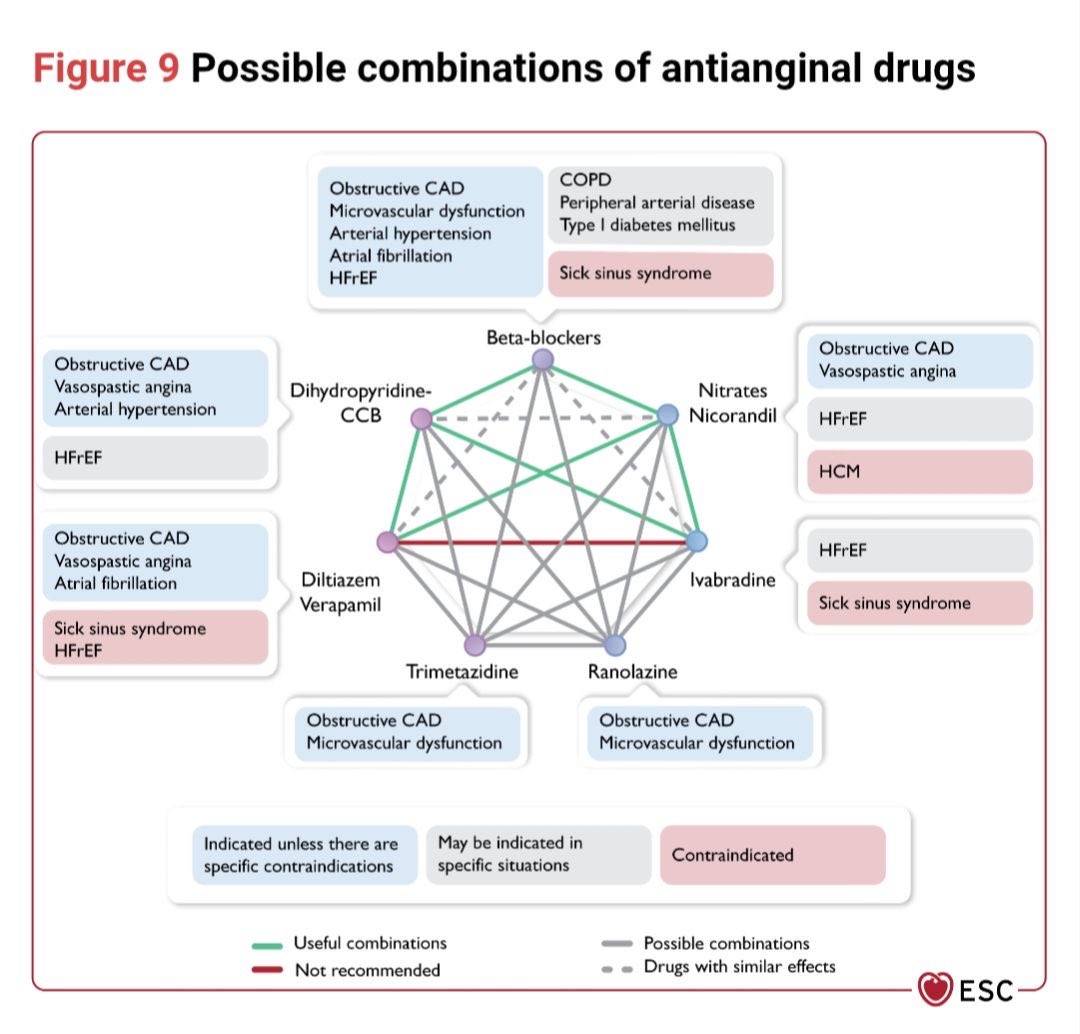

Combinaciones posibles entre diferentes Antianginosos en la práctica clínica 👇🏼 #CardioEd #ESC #Guidelines